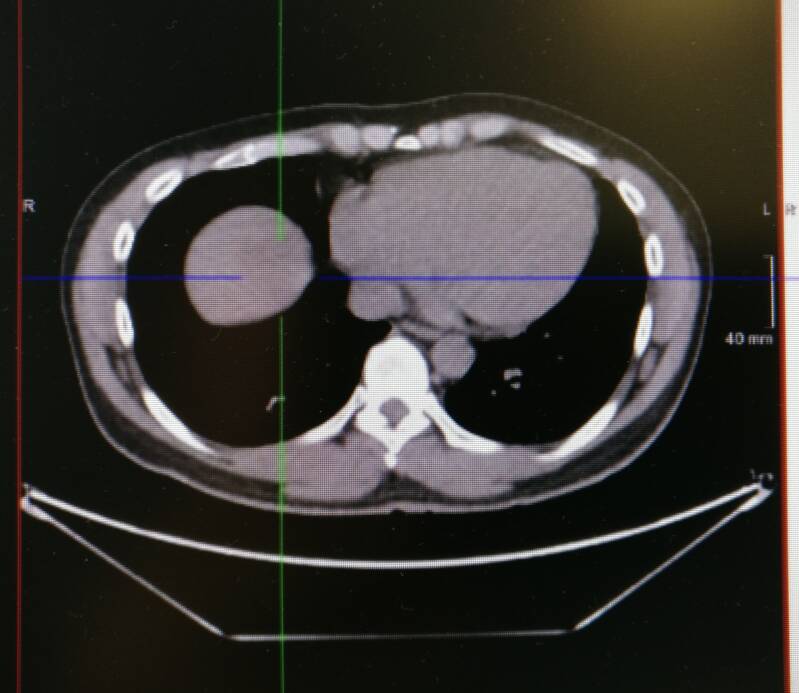

Het volgende plaatje is een CT-scan. Ik wordt hier dwars doorgesneden en we kijken van onderen naar boven. Deze doorsnede is gemaakt ter hoogte van de onderkant van her borstbeen. In het blauw-groene kruis zit mijn tumor. Rechts daarnaast is mijn hart. De witte stippen daaromheen zijn mijn ribben en onderin zie je een wervel. Het is meteen duidelijk dat enkel een CT-scan het moeilijk maakt om een tumor te ontdekken. De tumor is iets donkerder grijs dan het gezonde weefsel daaromheen, maar je moet goed kijken en op deze foto zie je het verschil bijna helemaal niet.

Daarom wordt met de CT-scan via de computer gecombineerd met de PET-scan. Het resultaat is een PET/CT-scan. Hierbij zie je duidelijk de tumor in mijn lever oplichten. Ook zie je dat mijn hart actief is en oplicht. De artsen kunnen letterlijk langs alle kanten door deze plaatjes scrollen en zo een duidelijk beeld krijgen van de vorm en de locatie van de tumor.